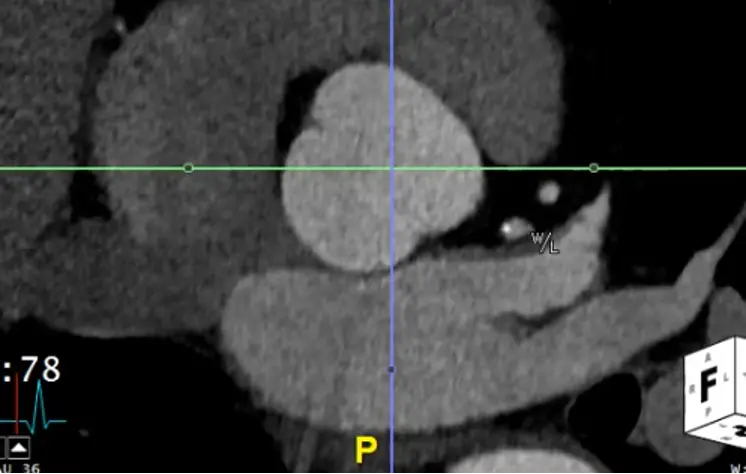

- Once youâve lined things up, in your axial view window you will now have what is called a âtrue short axisâ of the aorta at that level.

- Slide up and down to evaluate the AV anatomy. You will be able to determine if it is tricuspid, bicuspid, etc.

- Recall, the RCC is going to be the most anterior cusp. HINT: There is an âAâ (for anterior) at the top of the axial window and a âPâ (for posterior) at the bottom to help orient you.

- In the axial view, the âtrue short axisâ should be pretty close to appearing like a circle.